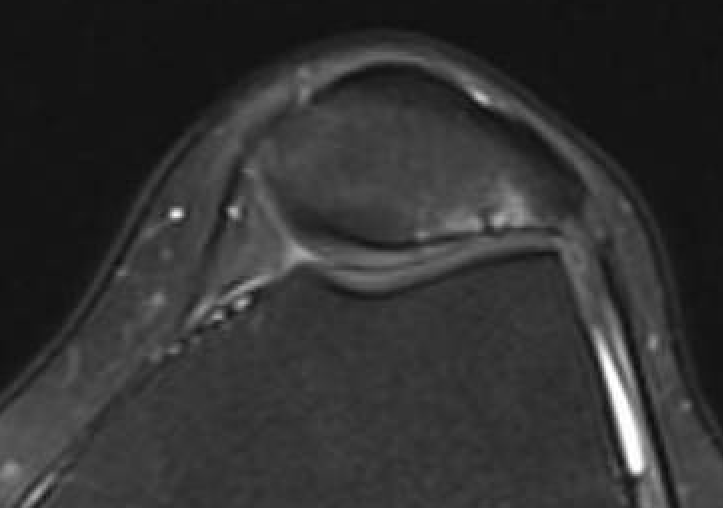

MRI

Moderate lateral facet PJF OA with tilt